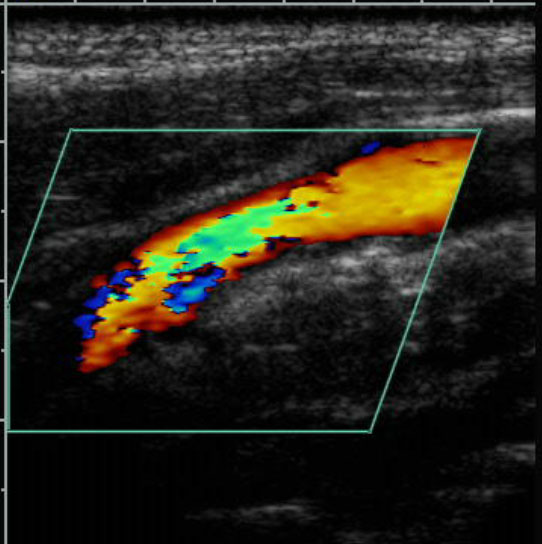

Vascular

Our Vascular app supports blood pressure, plethysmography and both non-imaging and full duplex ultrasound studies. All measurements flow from the ultrasound machine directly into the report. We also integrate with the Parks Flowlab equipment. The app covers all vascular report types.